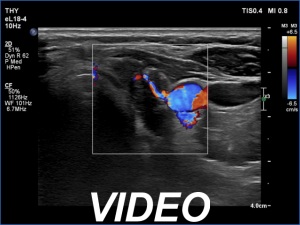

Ultrasonography. The thyroid was mainly composed of hypoechoic islets which floated in less hypoechoic background. These lesions had irregular, lobulated margins and showed no vascularity.

FNA was performed from a discrete lesion in the right and from another one in the left lobe. Cytology resulted in Hashimoto's thyroiditis. Wash-out thyroglobulin level exceeded 478 ng/mL in both cases.